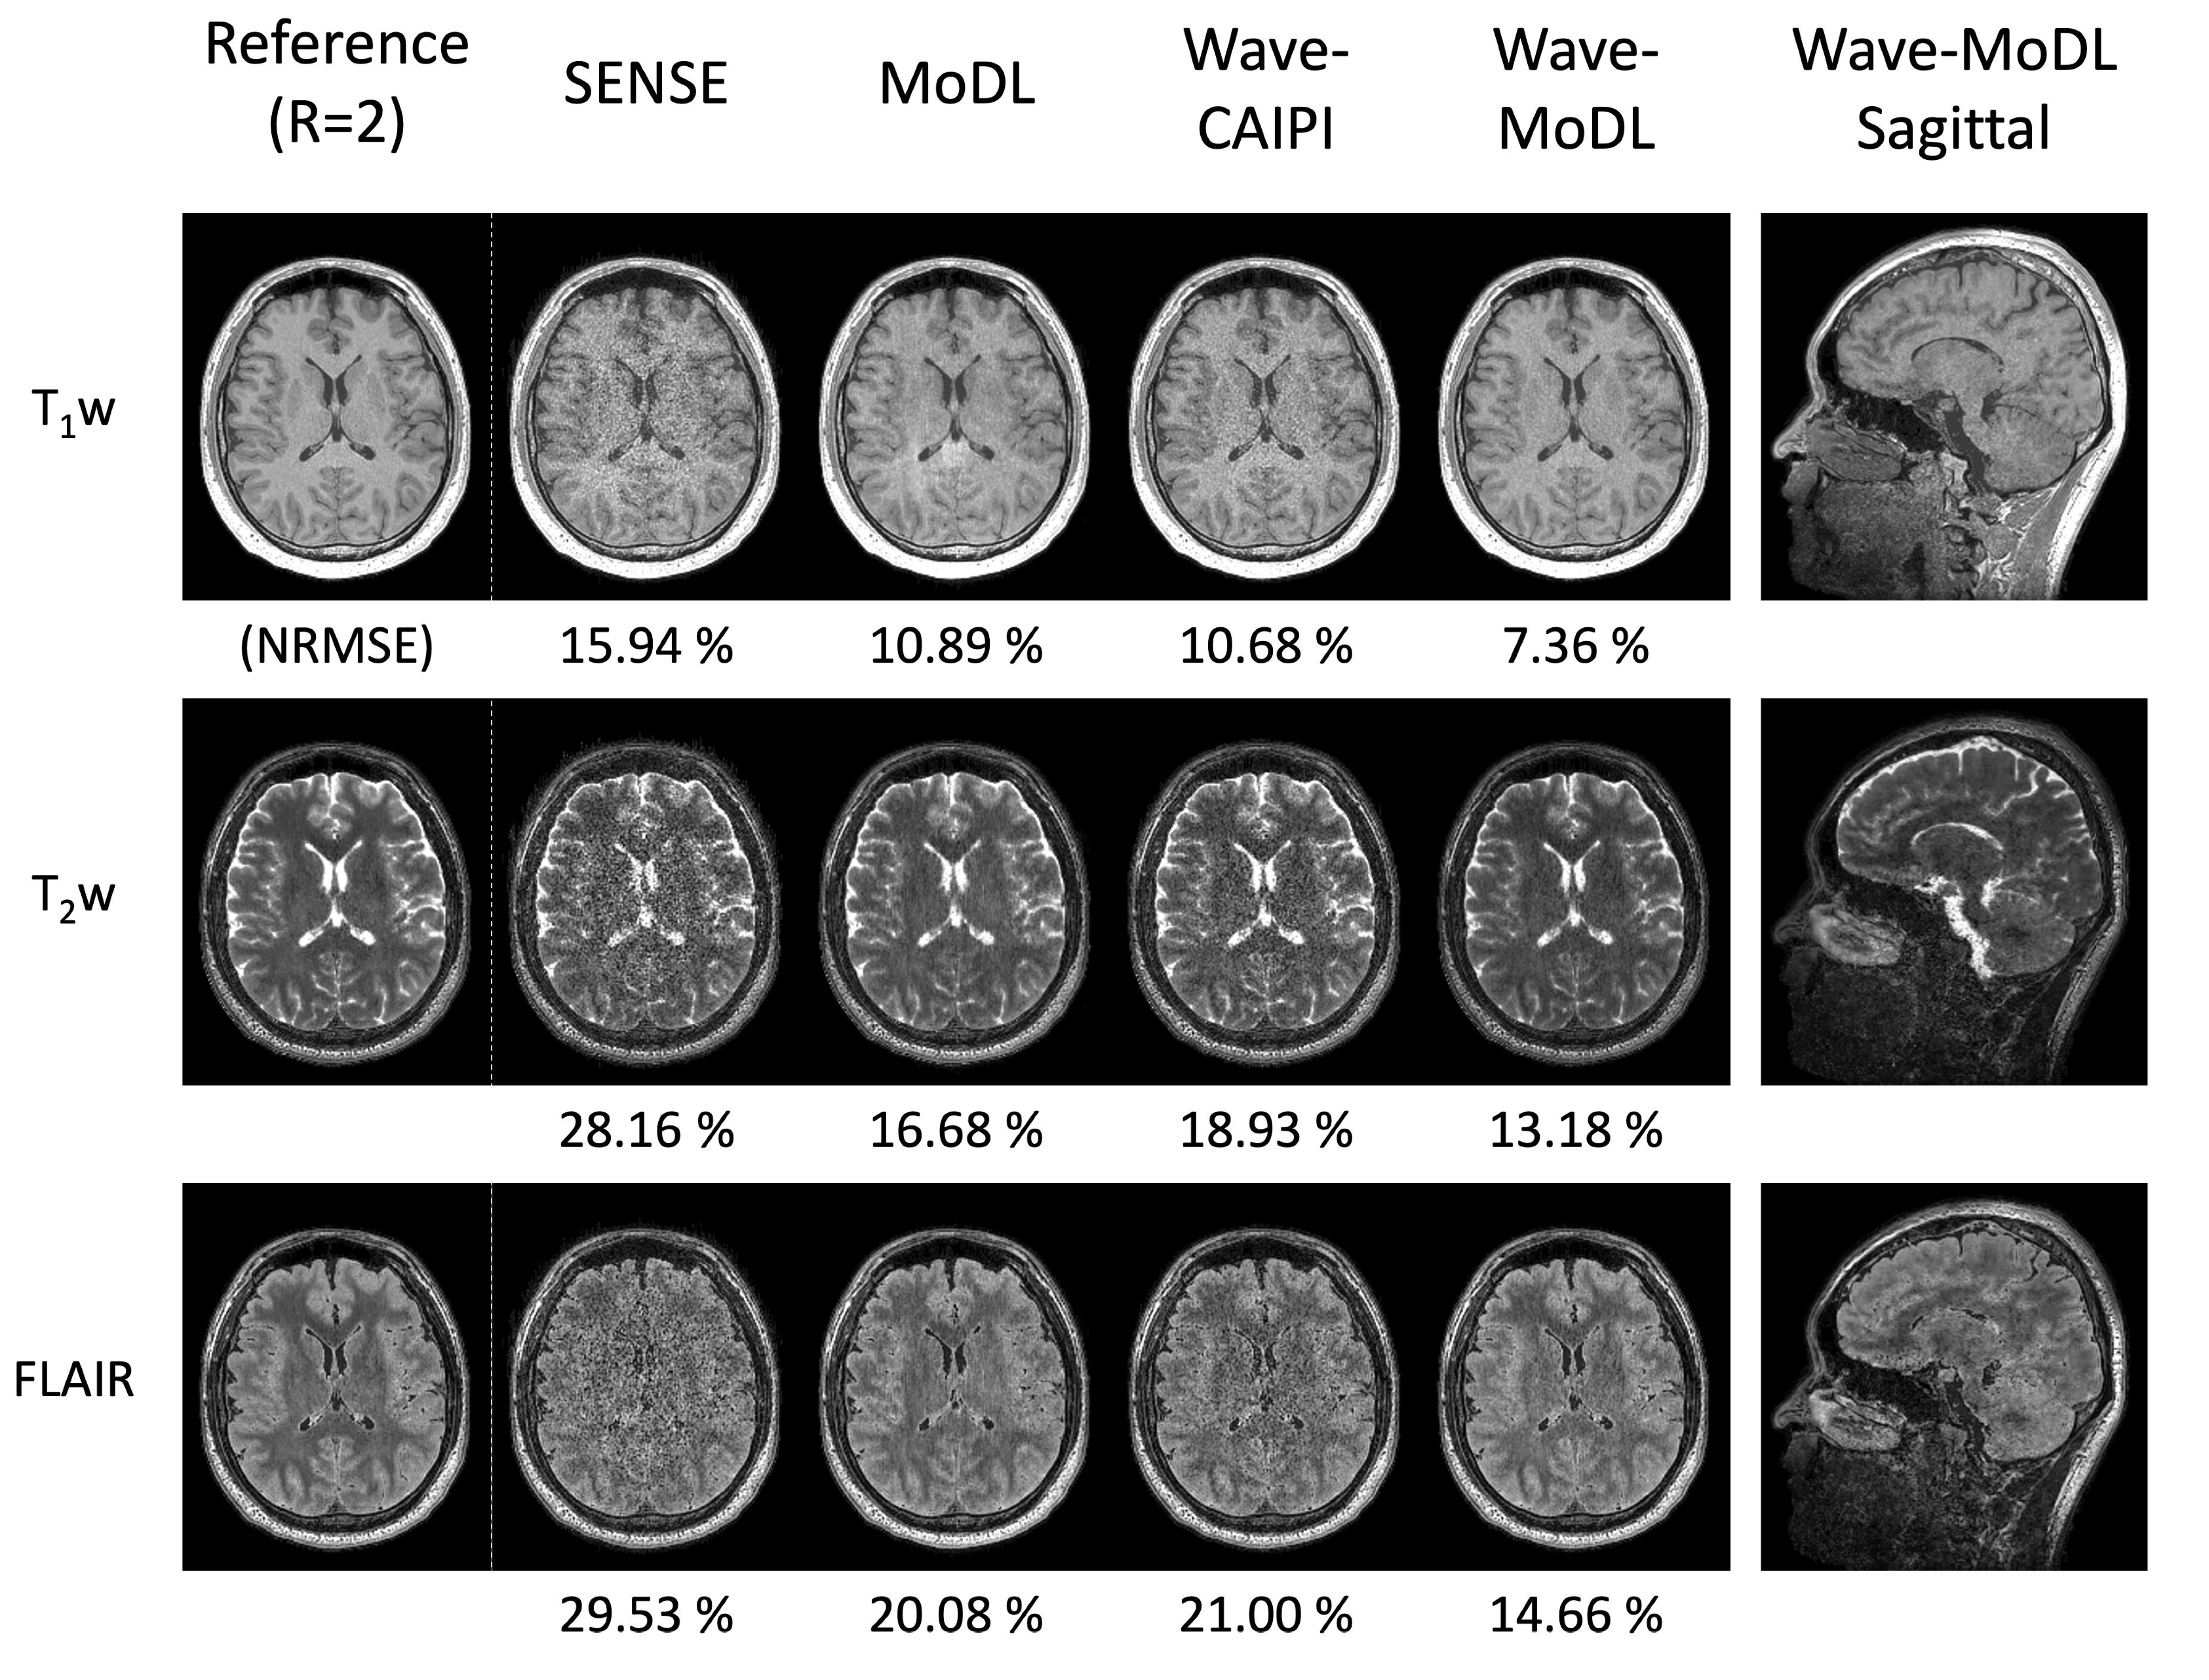

4.2. MEMPRAGE at R = 3 × 3